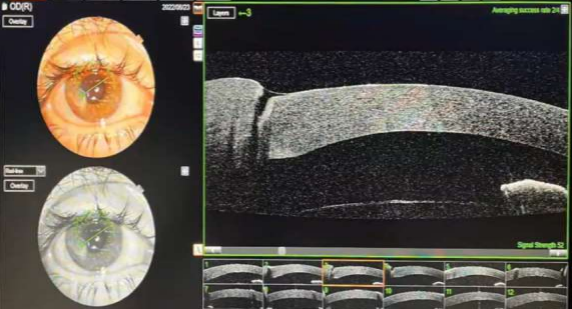

The OCT data of the 8:00 Meridian of Cornea  Fig 3

20 days after the trauma OCT data with the soft contact lens Fig 8

10 Months after trauma (sutures removed 2 months earlier), final OCT Data Note that the VA=0.5 (20/40) Fig 10